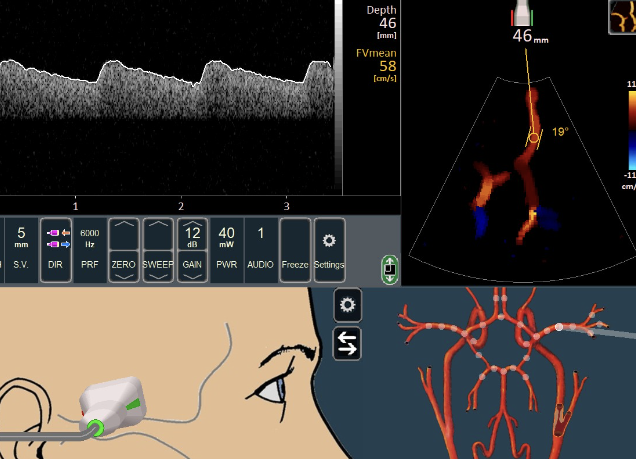

뇌혈류 초음파검사(TCD)

초음파로 뇌혈관의 협착, 폐쇄 유무와 혈류 속도, 혈류량 등에 대한 정보를 실시간 확인.